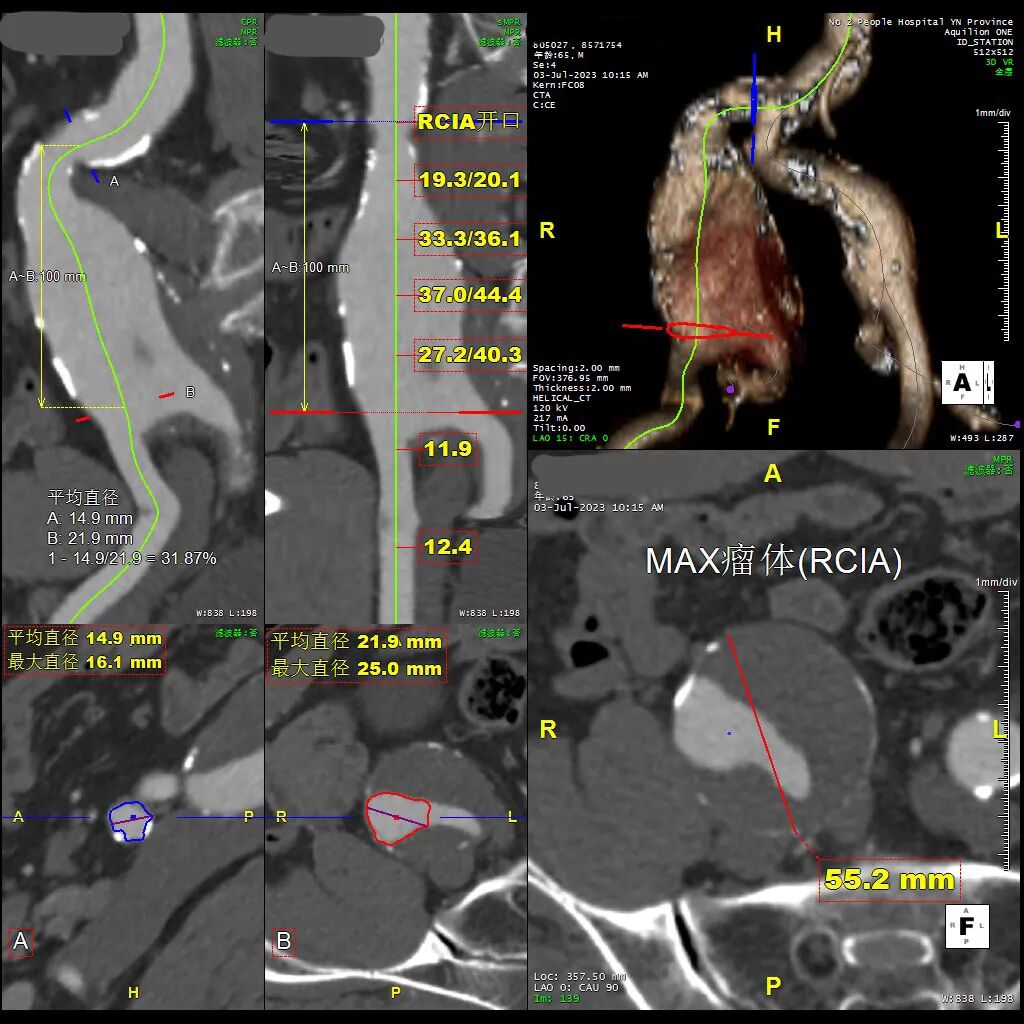

二、术前CT数据

患者入院后行CTA检查,CTA提示患者双侧巨大髂总动脉瘤,腹主动脉分叉以上血管直径正常。

双侧IBE植入对肾下倒髂内开口距离要求:

• 对侧要求>=165mm

• 同侧要求>=195mm